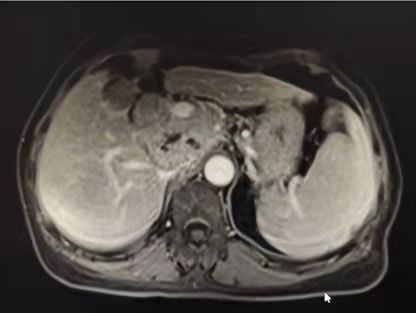

对肝癌患者来说,手术完成不是治疗的结束,患者和家属都要有打“持久战”的准备。术后应定期随访,复查内容包括肝脏影像学检查(腹部超声,必要时行增强磁共振)、甲胎蛋白(AFP)、肝功能和乙肝指标等相关检查。